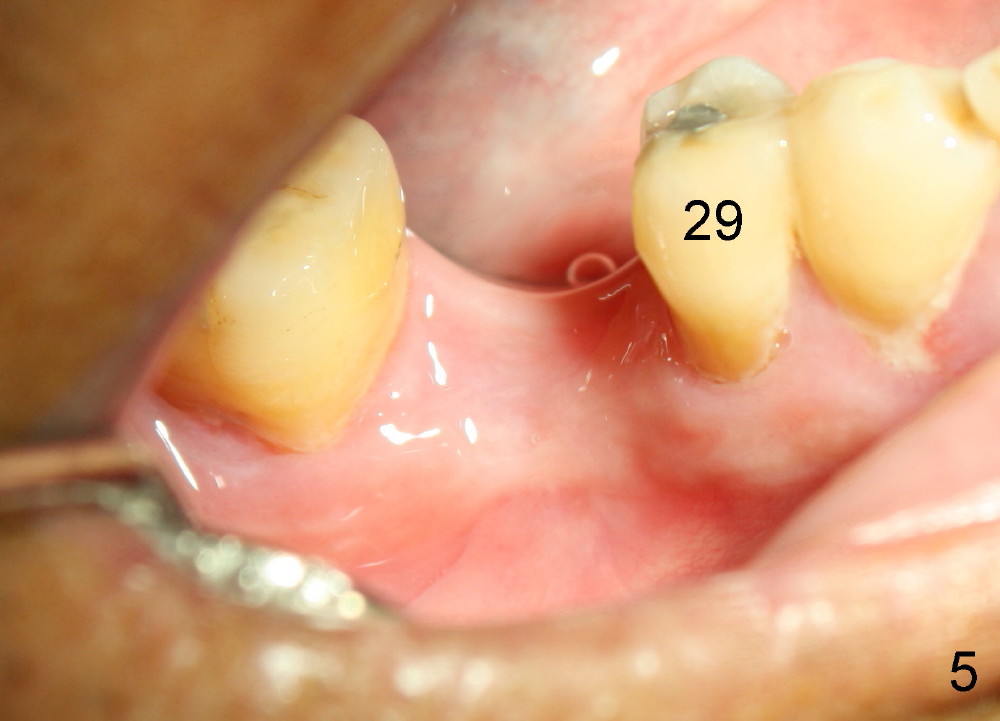

A 46-year-old man has severe periodontitis. The tooth #30 is complicated by incomplete root canal therapy (Fig.1,2). Three months after extraction (Fig.3-5: N: inferior alveolar canal), a 5x14 Tatum tapered implant is placed (Fig.6,7). The problem is that an implant driver is fractured (D in Fig.7), while the implant is being torqued. It takes time and effort to remove the fractured driver, but the implant is solid. The healing screw is placed without difficulty (Fig.8). Since the implant is placed lower than the lingual gingiva (L in Fig.9), a healing cuff is placed 1.5 months after implant placement (Fig. 10 and 11: C) to push the lingual gingiva down. The X-ray appears to show lower bone density around the implant (bone necrosis?), although the implant has no mobility at all. Since the implant is so solid, can we load it, two months after surgery? The lingual gingiva is now lower than the healing cuff (not shown). CT is scheduled to be taken tomorrow. Thanks.